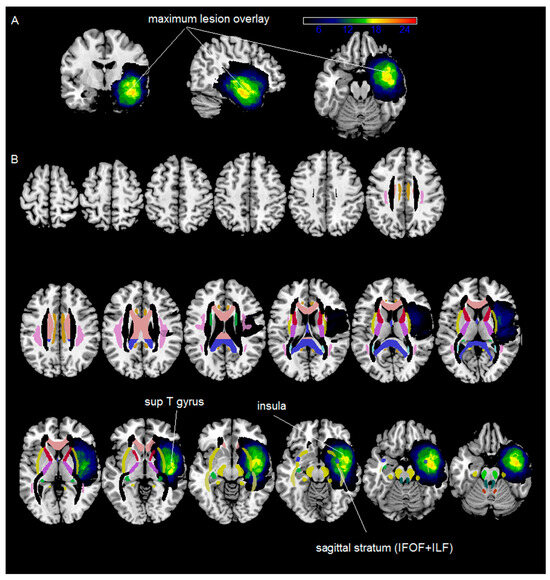

3.2. MRI Structural Data Analysis

| Area | N > 0 | %N > 0 | Max | MaxX | MaxY | MaxZ | % of Patients |

|---|---|---|---|---|---|---|---|

| Insula_LH | 14,128 | 1 | 19 | −46 | −5 | −1 | 73.07 |

| Temporal_Sup_LH | 20,488 | 0.811 | 19 | −47 | −5 | −1 | 73.07 |

| Amygdala_LH | 1965 | 1 | 18 | −34 | 3 | −20 | 69.23 |

| Temporal_Mid_LH | 19,609 | 0.555 | 18 | −46 | −1 | −26 | 69.23 |

| Temporal_Pole_Sup_LH | 9686 | 0.90 | 18 | −37 | 6 | −24 | 69.23 |

| Hippocampus_LH | 7133 | 0.93 | 18 | −37 | −6 | −20 | 69.23 |

| Temporal_Inf_LH | 23,508 | 0.82 | 17 | −45 | −5 | −26 | 65.38 |

| Temporal_Pole_Mid_LH | 8934 | 0.94 | 17 | −45 | 9 | −22 | 65.38 |

| Sagittal stratum | 2231 | 1 | 17 | 37 | −9 | −19 | 65.38 |